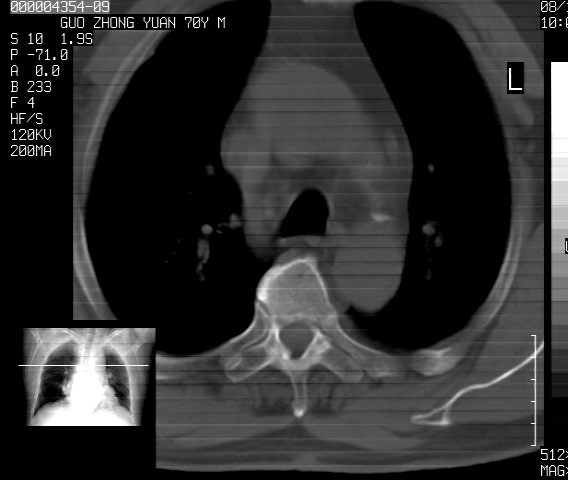

以下是引用sdzyy在2008-12-1 11:49:00的发言:[br]图像不全,请上传,右下肺炎症可能性大,占位待排.

以下是引用zjzjr在2008-12-1 14:53:00的发言:[br]图像不全,请上传,右下肺炎症可能性大,占位待排.心影增大,建议进一步检查.